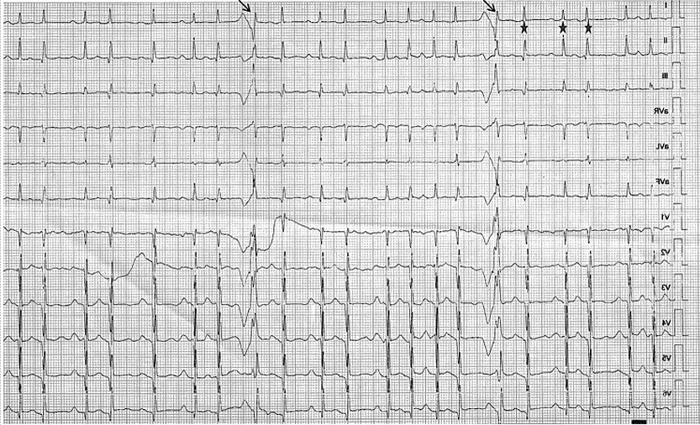

Em relação a esse ECG, nota-se que esse paciente se apresenta em ritmo de fibrilação atrial, e que os batimentos marcados pela seta se apresentam com QRS alargado, que ocorre devido à variação do comprimento do intervalo RR, marcados pelas estrelas, com ciclo longo seguido por um ciclo curto, com o próximo complexo QRS conduzido com aberrância pela variação do período refratário do feixe de His. Este fenômeno é denominado de